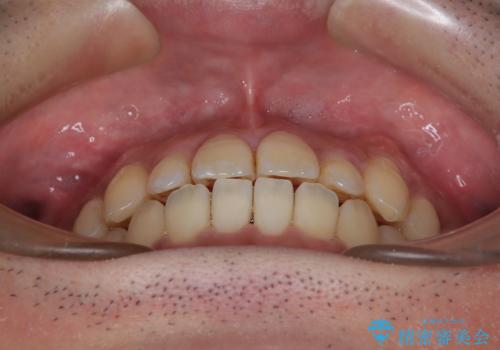

- 前歯のデコボコとクロスバイトを治したいとのことで来院された患者様です。

上下顎ともに歯列全体の側方拡大とIPR(歯と歯の間を削る)によってデコボコとクロスバイトが解消するように設計し、インビザラインにより治療を行うこととしました。

反対咬合特有の治療途中の前歯の干渉が長く続き、治療中に食事をとりにくく、ご迷惑をおかけしました。

前歯の咬み合わせの調整などを行い、安定した咬み合わせに仕上げることができました。